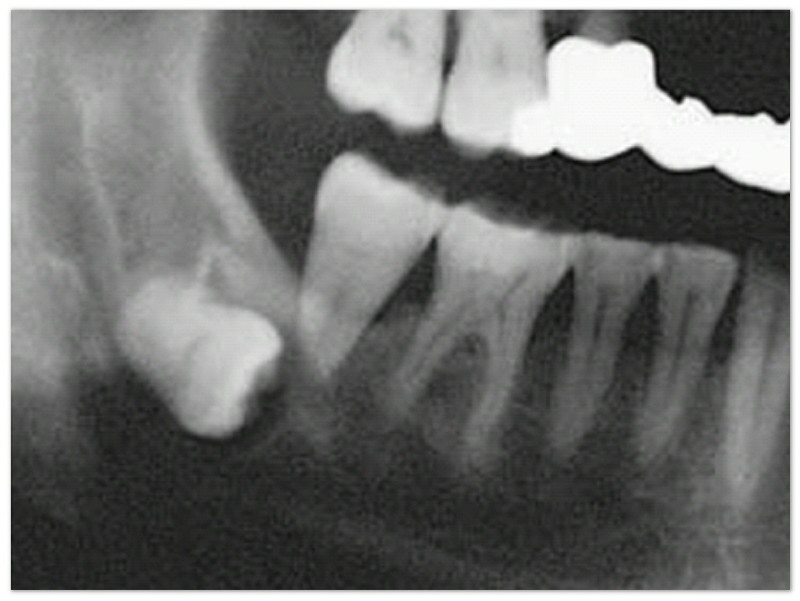

Gigi impaksi atau tidak bisa tumbuh.

Gigi yang tidak bisa tumbuh kadang baik-baik saja, kadang pula bisa menimbulkan masalah. Apabila di usia 17-21 tahun tidak ada tanda-tanda gigi yang mau tumbuh, lebih baik datang ke dokter gigi untuk memastikan ada atau tidaknya benih gigi bungsu. Lebih baik mencegah daripada mengobati kan? 🙂

Gigi bungsu yang tidak bisa tumbuh bisa menjadi pencetus terbentuknya abses (apabila terinfeksi), tumor, atau kista.

Gigi bungsu sering tumbuh dengan arah miring ke depan, sehingga mendorong gigi-gigi di depannya dan membuat gigi di depannya menjadi berantakan. Oleh karena itu, apabila ingin menggunakan kawat gigi, dokter gigi sering menganjurkan pengambilan gigi bungsu yang menjadi penyebab gigi berantakan.

Merusak akar gigi sebelahnya.

Selain menyebabkan gigi berantakan, gigi bungsu yang arah tumbuhnya ke depan juga dapat menyebabkan gigi di sebelahnya menjadi rusak.

Yang pertama tentu saja dengan cara rutin kontrol ke dokter gigi. Di sekitar umur 12-15 tahun, mahkota gigi bungsu sudah terbentuk sempurna sehingga dapat terlihat apabila dilakukan foto radiograf. Dari foto radiograf tersebut, dokter gigi bisa memprediksi dapat atau tidaknya gigi bungsu tersebut tumbuh dengan maksimal.

Apabila kemungkinan besar gigi tersebut akan menimbulkan masalah, dapat dilakukan tindakan pencabutan pencegahan (pada usia kurang dari 20 tahun). Pencabutan pencegahan ini lebih menguntungkan karena akar gigi sulung masih pendek, tulang lebih lunak, sehingga penyembuhan pun akan lebih cepat.